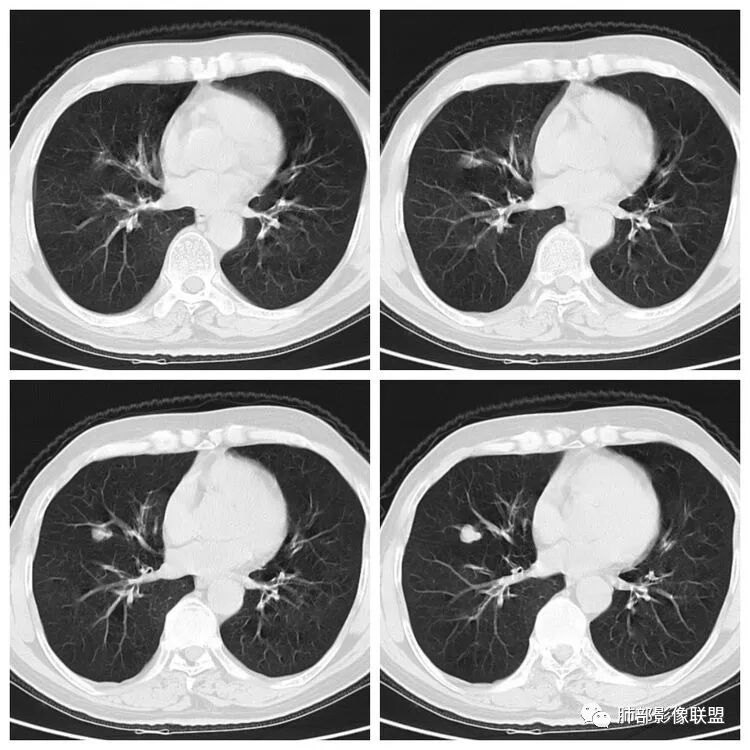

年龄:66岁婚姻:已婚入院日期:2017-12-07病情陈述者:患者本人主诉:发现右中肺占位1天。现病史:患者自诉于昨日在我院门诊体检行胸片示:右下肺野结节,性质待定,建议进一步检查。故完善胸部CT示:右中肺外侧段结节灶:肺癌可能。建议住院治疗。患者诉无胸痛、胸闷、发热,无咳痰、痰血、咯血、盗汗、乏力、呼吸困难,无声音嘶哑、饮水呛咳、吞咽困难、头痛、恶心、呕吐、骨痛。今为进一步治疗,门诊以“右中肺占位收入院。患者病后精神状态一般,食欲一般,睡眠良好,大便正常,小便正常,体力情况良好,体重无明显变化。既往史:有“高血压病”病史6年,“脑出血”病史6年,“胃镜下行胃息肉切除”病史6年,“腰椎压缩性骨折手术史”半年,否认肝炎、结核、疟疾病史,否认心脏病史,否认糖尿病、精神疾病史,否认输血史,否认食物、药物过敏史,预防接种史不详。个人史:生于长沙市雨花区高桥火焰开发区十组,久居本地,否认血吸虫疫水接触水,有吸烟史38年,每日达30根左右,未戒烟。无饮酒史,否认毒物接触史。

1.老年女性,没有明显临床症状。

2.体检发现右肺中叶孤立性肺结节,边缘光整,有浅分叶,没有明显的毛刺及收缩牵拉。

3.密度均匀,周围干净。

4.近端支气管似乎有截断。